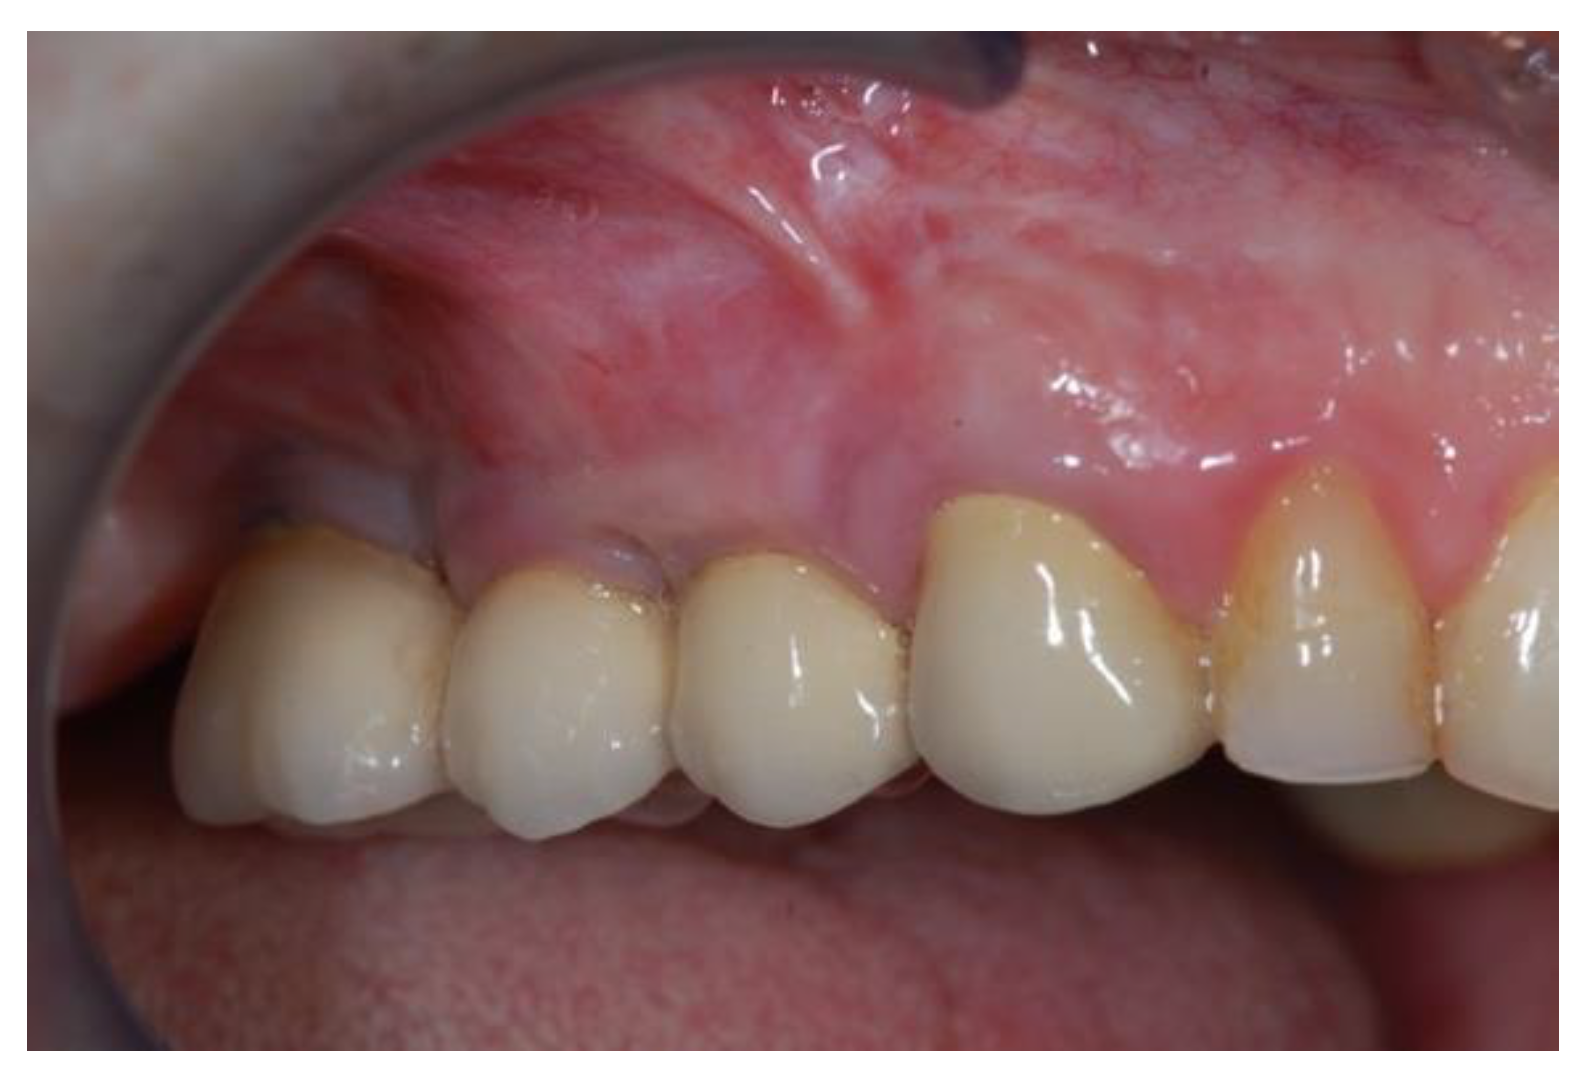

2.1. Surgical Procedures

2.2. Follow-Up

3. Results